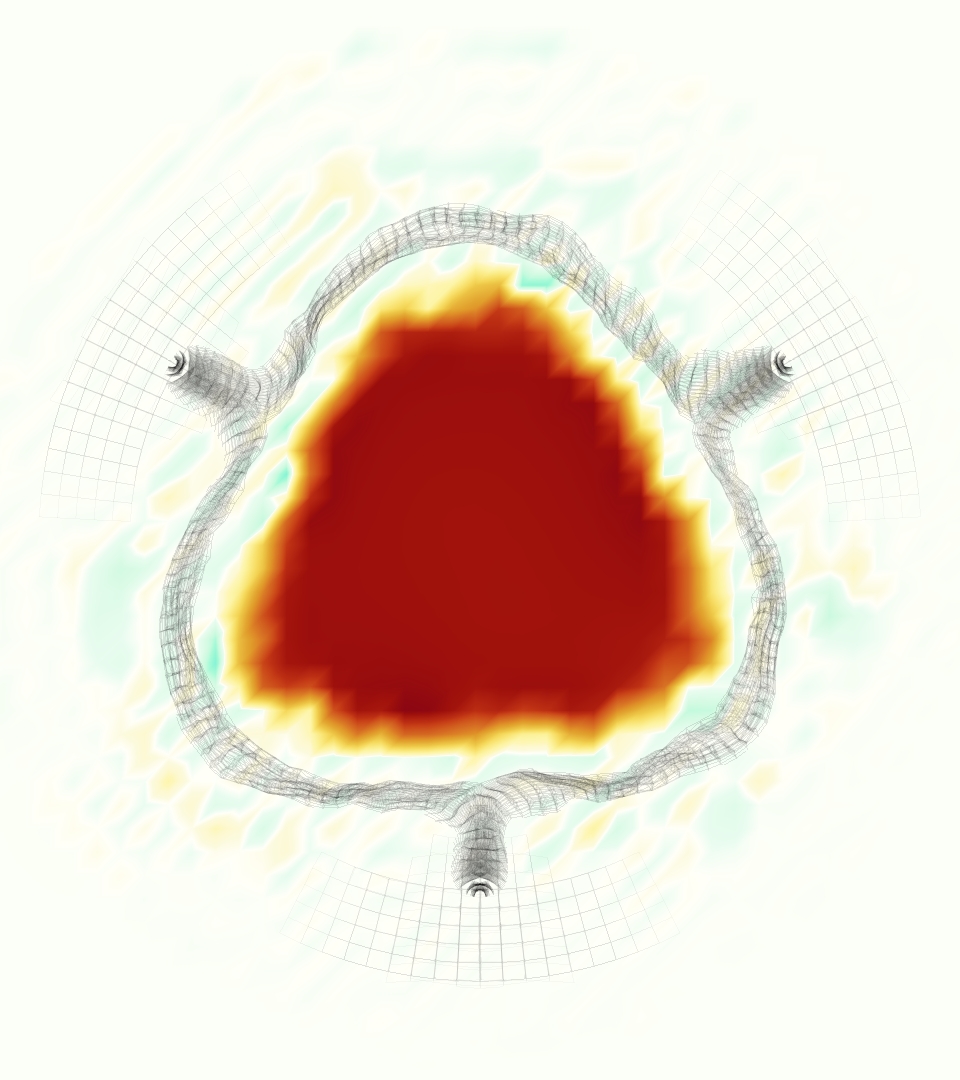

The gross morphology of the model valve that emerged from this process is shown in Figure 4. The free edge was 2.87 cm, corresponding to 3.3 cm in the predicted loaded configuration. After the pinching the leaflets together at the commissures, this left approximately 2.1 cm of free edge rest length per leaflet free to move independently of the other leaflets, within measurement error of ±0.1 cm from the free edge length of 2.2 cm measured on the prostheses. The leaflet rest height was 0.94 cm corresponding to a predicted loaded height of 1.44 cm. The measured leaflet height of 1.3 cm is nearly the predicted loaded height of 1.44 cm, which may be because the leaflets are so compliant in the radial direction, that pulling them flat to measure them achieved substantial stretches. The fiber orientation of the model runs from commissure to commissure and qualitatively matches experimental observations [38], though direct quantitative comparison is beyond the scope of this work. One minor limitation is that we do not add bending rigidity to the leaflets, beyond what emerges from the thickening process described above, and thus may not accurately capture leaflet flutter or other similar behaviors. Based on the thickness of mm, we estimated the mean tangent modulus at the predicted loaded stretches as dynes/cm2 circumferentially and dynes/cm2 radially. The prosthetic valve tissue is fixed in glutaraldehyde, and literature values for the fully-recruited circumferential tangent modulus of fixed porcine aortic valve tissue vary widely. Based on the experimental measurements of Billiar and Sacks and their constitutive law for valves fixed under 4 mmHg of pressure, we evaluated their constitutive law at the relevant stretches and and estimated the circumferential tangent modulus to be dynes/cm2 [6]. Rousseau et al. reported moduli ranging from to dynes/cm2, depending on the applied preload during fixation [36]. Sung et al. reported moduli ranging from to dynes/cm2, depending on fixation pressure [43]. Thus our estimated tangent modulus falls within the range of existing studies, so we considered our resultant modulus in good agreement given the complexity of the steps involved, phenomenological nature of the constitutive law and uncertainties in experiments. We do not have access to the precise material properties of the prosthetic valve, and further, the only literature we could find on the material properties of a similar prostheses reported the tangent modulus at one particular loading, which did not appear to be at a relevant stretch for comparisons with our model [19]. Thus, our model has material properties in a reasonable range for a fixed aortic valve prostheses (placed in the pulmonary position in our simulations), but it does not directly model the material properties of the prostheses.

We constructed the model vessel for FSI simulations from data from the MRI scans (Figure 4). The signal magnitude of 3D printed model material is distinct from the signal of the fluid in the scans, and we applied a thresholding operation to generate a three-dimensional model of the printed vessel surface. Using the MRI data ensured that the MRI and simulation coordinates were consistent in space and there were no alignment or registration errors. While using the files that generated the 3D printed model would have offered more spatial fidelity, the potential error in flow fields due to any mis-registration would have likely been much more substantial. Using Meshmixer (San Rafael, CA), we smoothed the mesh to remove stair-step effects and removed artifacts from the valve scaffold. We then remeshed to the desired edge length of 0.25 mm and extruded the model 0.25 mm and 0.5 mm to create a three-layer structure. As in the valve, this serves to eliminate the “grid aligned artifact” that can occur with pressure differences across thin membranes in the IB method [16]. Flow extenders of length 1 cm were added to the vessel at the inlet and both outlets to ensure that the normal to the vessel was aligned with the normal of the fluid box at the inlets and outlets. In FSI simulations, the vessel was held in place using target points, stiff springs of zero rest length that connect the current position of each model node to its desired position (Section 3.3). Additional linear springs are placed on each edge in the triangulated model. These springs are not meant to model a particular material and only serve to keep the vessel rigid and stationary throughout the simulation.

At = 0, the axial slice directly at the valve annulus shown in columns 1 and 2 in Figure 6, there was excellent agreement between the simulation and experiment over the cardiac cycle in the speed and shape of the jet through the valve. In both cases, the axial velocity increased as the flow accelerated during systole and the valve leaflets opened, then decreased during diastole with slight negative velocity before the valve leaflets were fully closed. The forward flow through the valve annulus did not form a full circle, but rather developed a triangular shape with a point of the triangle forming along the interior curve of the vessel, at the bottom of the axial slices. At = 0, the points of this triangular jet shape aligned with the commissures of the valve. This shape persisted during peak systole and was well-matched by the simulation.

The axial slice = 0.625 cm, shown in columns 3 and 4 in Figure 6, cut through the support scaffolding of the valve and the leaflets when they are open. In the experimental data, the shape of the jet changed as it moved downstream. A triangular shape occurred, but the points were then aligned with the middle of each open leaflet as opposed to the commissures. Those points were also more rounded than they were at = 0. The peak velocity of the jet was faster at = 0.625 cm than at = 0, as the flow accelerated through the open valve leaflets. The simulation produced these features at = 0.625 cm. The triangular shape of the jet shifted similarly, and its speed increased compared to the upstream slice. As the flow decelerated into diastole, the jet shape remained roughly triangular but diminished in intensity before disappearing after valve closure.

The jet continued to develop at = 1.25 cm, an axial slice immediately downstream of the valve scaffolding and open leaflets, shown in columns 5 and 6 in Figure 6. In the experimental data, the points of the triangular jet shape extended further towards the vessel wall. In addition, regions of reversed flow developed in the locations downstream of the commissures, resulting in curved sides to the shape of the jet. Each tip of the jet was unique, due to variations in the individual leaflets in the physical bioprosthetic valve. These variations are apparent in the velocity fields, possibly because the jet edges are similar enough cycle to cycle that irregularities are still being captured even with phase averaging. Further discussion of these features can be found in Schiavone et al. [39], which showed that the jet tip shapes occurred in different pulmonary anatomies, demonstrating that they were likely due to inherent properties of each leaflet. The leaflets in the mathematical model of the valve are identical, so these nuances in leaflet variation could not be replicated. The simulation did capture some of the extension of the tips of the jet, as they were closer to vessel wall at slice = 1.25 cm than = 0.625 cm. The curves in the triangular sides of the jet were also present in the simulation, though they were less pronounced than the experimental data. At both = 0.625 cm and = 1.25 cm, the jet shape in the simulation was smoother than the jet in experiment. It is possible that the free edges of the leaflets in the mathematical model are not fully replicating the behavior of the physical leaflets of the bioprosthetic valve, in particular the amplitude or frequency of leaflet flutter, leading to the variations seen in the jet shape at = 1.25 cm downstream of the leaflet edges. The simulation, however, does capture the key features of the triangular shape and speed of the jet. Overall, qualitative comparisons demonstrated that the simulation reproduced key features of the flow during systole and diastole.